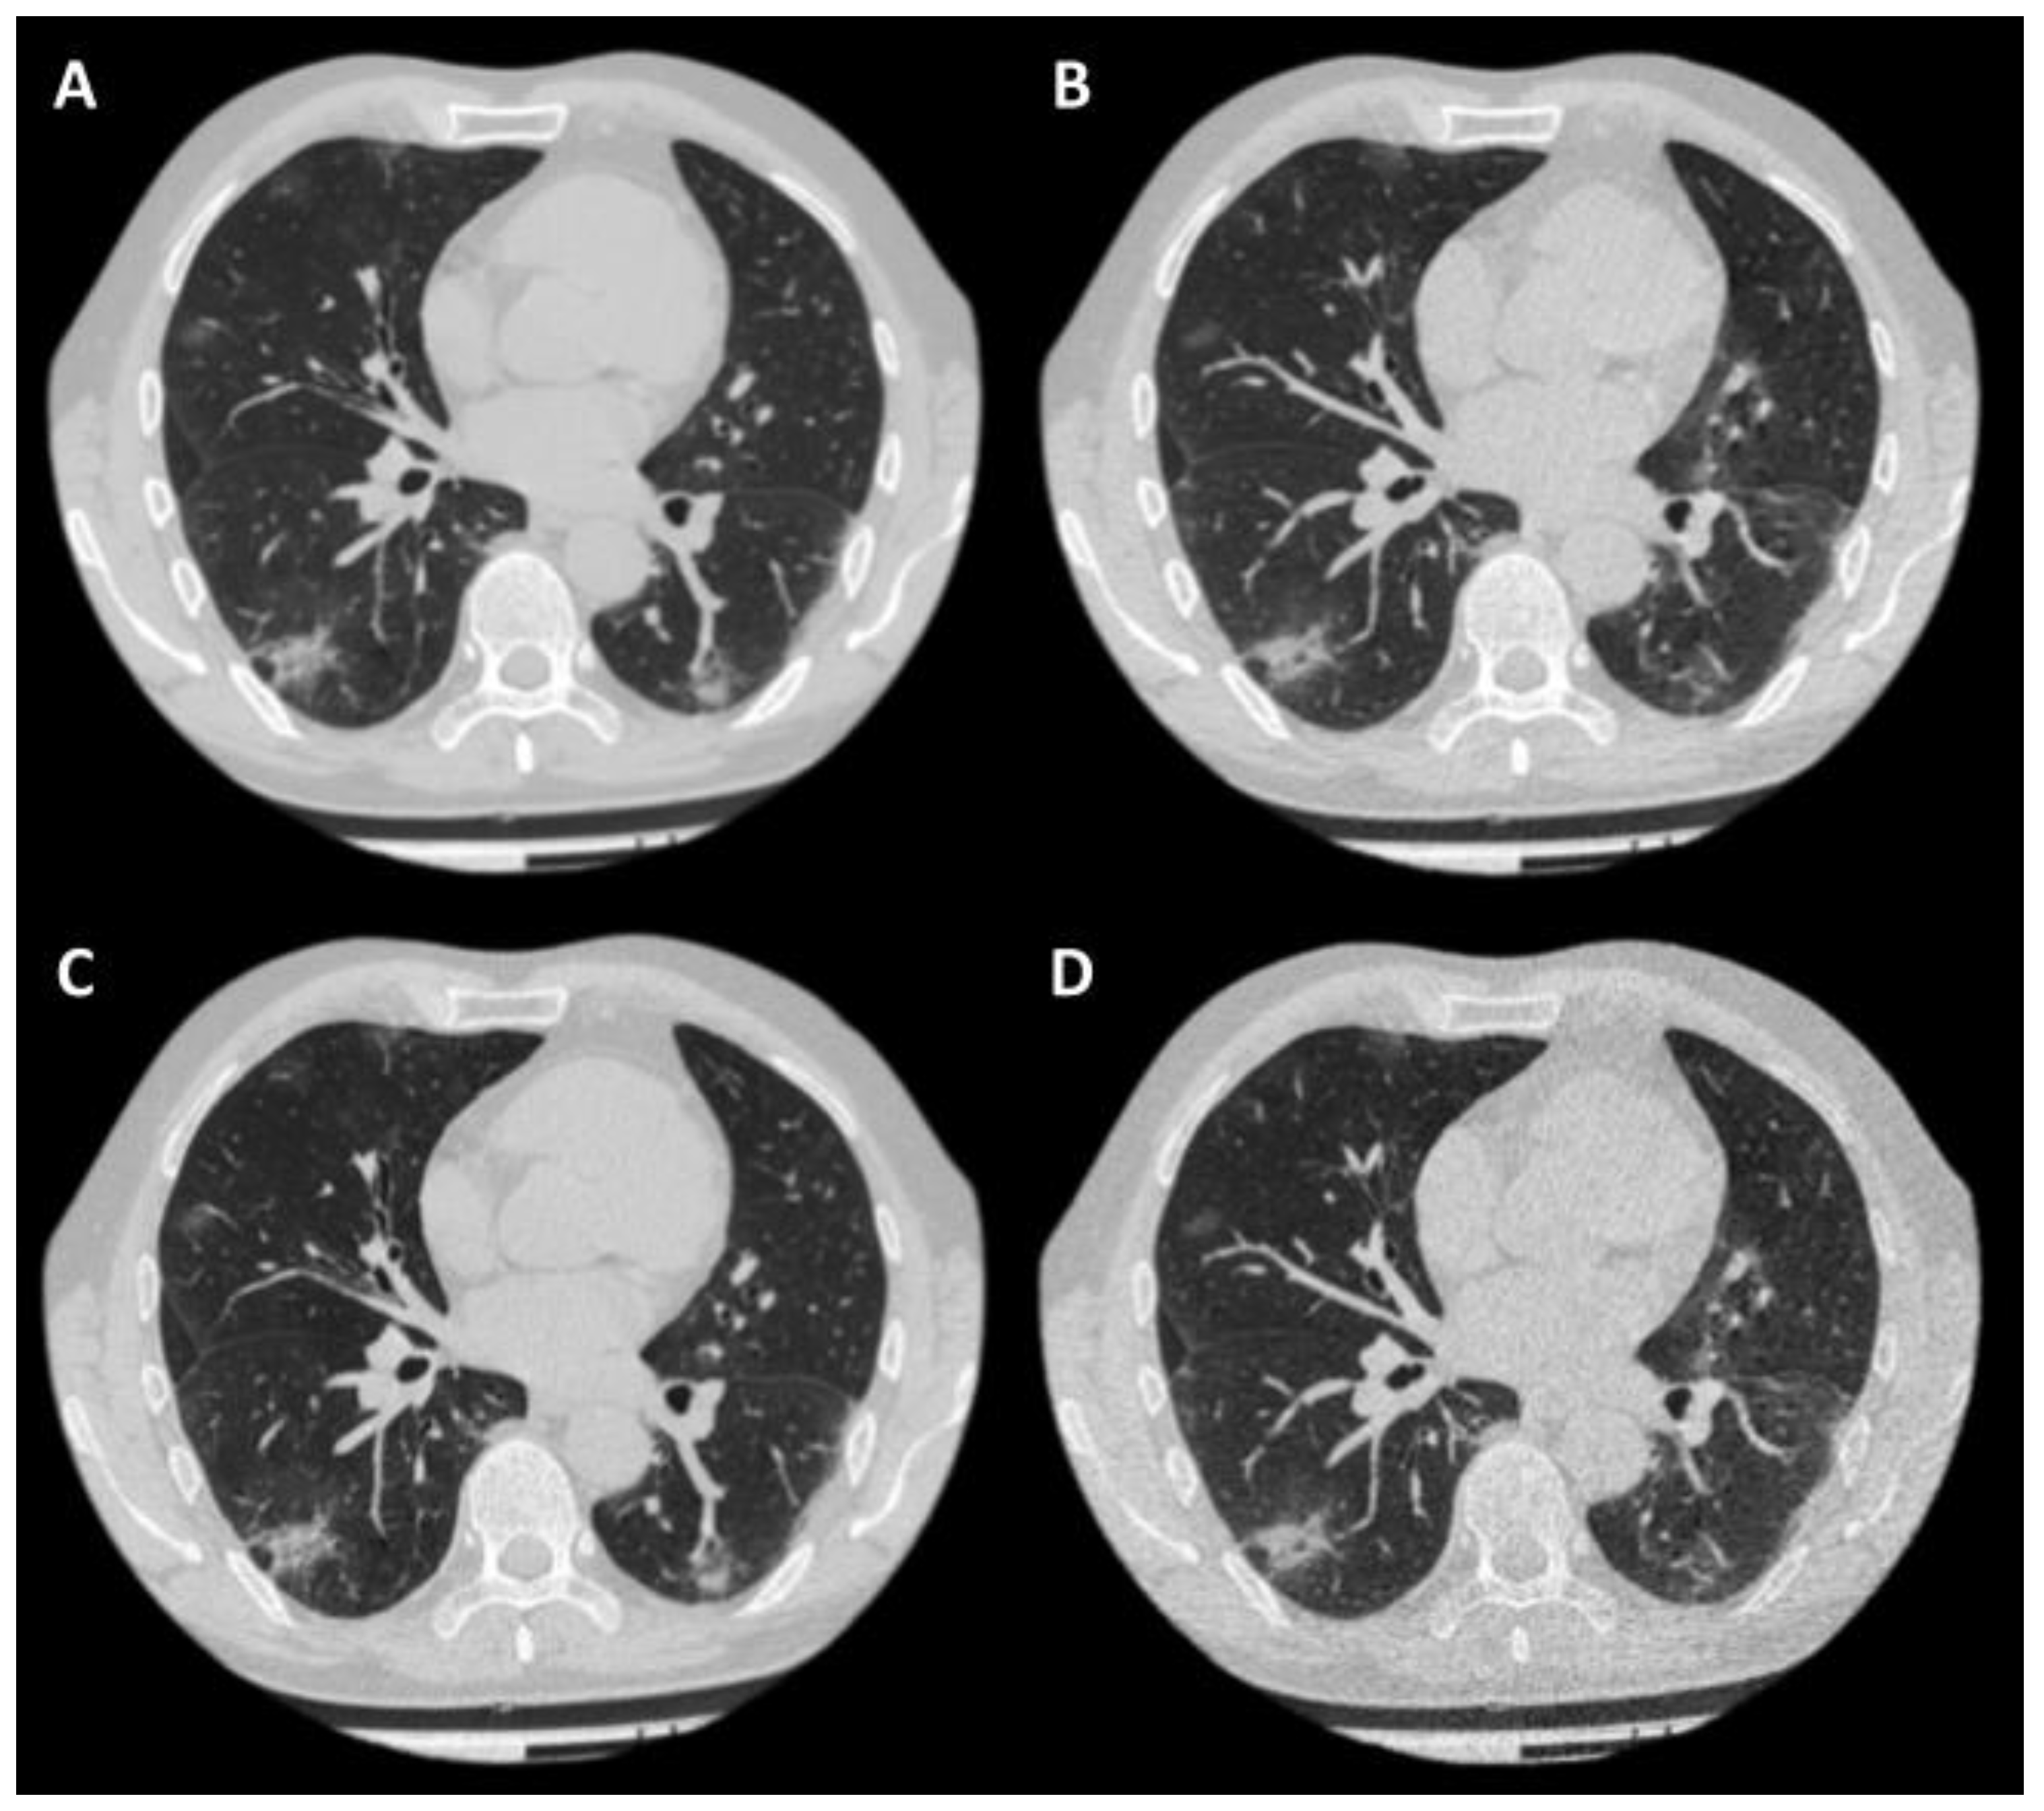

3.3. Image Analysis